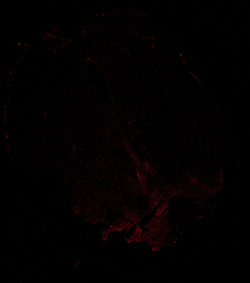

TH

6PCW human midbrain